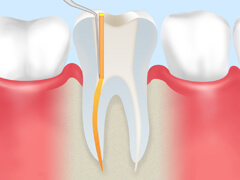

根管治療とは、歯の中にある「根管」という細い管の中から、虫歯菌に冒されて死んでしまった神経や血管を取り除き、内部をきれいに洗浄・消毒して薬剤を充填する治療です。根管はとても細かく複雑に枝分かれしているため、この治療は簡単ではありません。しかし、確実に行えれば歯を残すことができるのです。

| 虫歯菌に冒されて死んでしまった神経・血管を除去します。 | 根管の長さを正確に測ります。 | 根管内に汚れが残らないよう、歯の内部をきれいに洗浄します。 | 薬剤を使って、内部を殺菌・消毒します。 | すき間ができないよう、薬剤をすみずみまで充填します。 | 土台を入れ、上部に被せ物を装着して治療完了です。 |